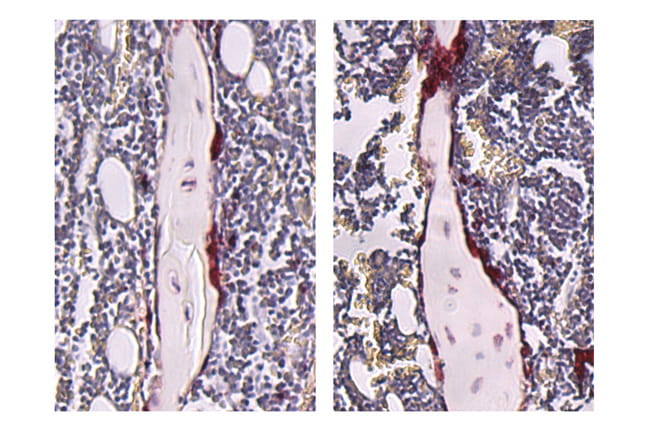

Stained tibiae from germ-free (left) and SFB-mono- associated (right) mice.

Stained tibiae from germ-free (left) and SFB-mono- associated (right) mice. Mice colonized with SFB displayed an increase in osteoclasts (stained red), which resorb bone.